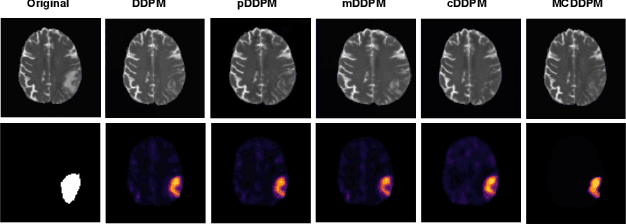

Abstract:Detecting anomalies in brain MRI scans using supervised deep learning methods presents challenges due to anatomical diversity and labor-intensive requirement of pixel-level annotations. Generative models like Denoising Diffusion Probabilistic Model (DDPM) and their variants like pDDPM, mDDPM, cDDPM have recently emerged to be powerful alternatives to perform unsupervised anomaly detection in brain MRI scans. These methods leverage frame-level labels of healthy brains to generate healthy tissues in brain MRI scans. During inference, when an anomalous (or unhealthy) scan image is presented as an input, these models generate a healthy scan image corresponding to the input anomalous scan, and the difference map between the generated healthy scan image and the original anomalous scan image provide the necessary pixel level identification of abnormal tissues. The generated healthy images from the DDPM, pDDPM and mDDPM models however suffer from fidelity issues and contain artifacts that do not have medical significance. While cDDPM achieves slightly better fidelity and artifact suppression, it requires huge memory footprint and is computationally expensive than the other DDPM based models. In this work, we propose an improved version of DDPM called Multichannel Conditional Denoising Diffusion Probabilistic Model (MCDDPM) for unsupervised anomaly detection in brain MRI scans. Our proposed model achieves high fidelity by making use of additional information from the healthy images during the training process, enriching the representation power of DDPM models, with a computational cost and memory requirements on par with DDPM, pDDPM and mDDPM models. Experimental results on multiple datasets (e.g. BraTS20, BraTS21) demonstrate promising performance of the proposed method. The code is available at https://github.com/vivekkumartri/MCDDPM.